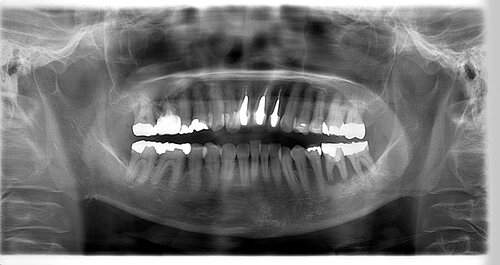

インプラント治療の症例1

レントゲン写真

- 透過像

| 年齢 | 50代・男性 |

|---|---|

| 主訴 | 右下歯が疼く |

| 治療内容 | ・右下6番インプラント ※1:FGG(遊離歯肉移植術)とは、足りない歯ぐきを上顎から上皮を切り取り移植する外科手術 |

| 治療費 | 合計:902,000円(税込) ■内訳 |

| 治療期間 | 9ヵ月 |

| 治療方針 | 右下の当該歯は歯根破折により保存不可能と診断しました。歯周疾患も伴っていたため抜歯後に骨吸収※1が大きく起こることが予測できました。チタンメッシュ併用骨再生誘導法(GBR※2)を選択しインプラント埋入と同時に行い自然な歯槽骨のラインを再現しました。またGBRを行う際にインプラント辺縁の付着歯肉の減少が起こる為、遊離歯肉移植術(FGG※3)を行い清掃性を考慮した形態に仕上げました。 ■治療方針の解説 治療した右下の歯をレントゲンで撮影したところ根本の部分に黒く写る箇所があり「根尖性慢性周囲炎※1」と診断。また歯周病も進行していました。 ※1 骨吸収・・・歯槽骨という歯を支える骨がなくなっていくこと |

| 担当者所見 | 主訴の右下だけでなく歯茎の腫れ、発赤があり不良補綴や不良充填など他にも治療箇所が多数ありました。プラークコントロールが不良であった為まずはブラッシング指導を行いセルフケアの重要性を理解していただくところからスタートしました。 右下6番の歯はインプラント治療を行なった結果審美的にも機能的にも患者様の満足を得ることができました。骨造成と歯肉移植も行なった為インプラントを支える十分な歯周組織の獲得ができたと思っております。 |